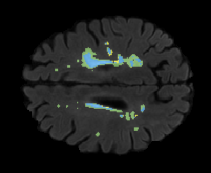

FLAIR

[Uncaptioned image] [Uncaptioned image] [Uncaptioned image]

T1

Ground Truth

Unimodal

Offline synthesis

Proposal

Table 2: Segmentation results for all proposed methods, each column represent a different slide in the image, blue areas are regions which were correctly labeled, false positives are shown in green, and false negatives in yellow

In order to better understand the above results, we visually analyzed the output segmentation performed for each method. Table 2 shows the results for three different slices (one slice per column). As illustrated, the proposed method is able to produce less false positives. It is also important to note that, unimodal segmentation is the one that produces more false positives, showing the advantage of using synthetic data. Regarding the nature of false positives, it can be easy to see in the third column a large number of false positives are on the border of periventricular lesions for the Unimodal method in comparison to the proposed method. Also from the first and second column, it can be observed that Unimodal tend to produce more small regions of false positives near to cortical areas. Removing such false positives requires additional post-processing steps, therefore, it is of value avoid this kind of over-segmentation. It can also be noted that synthesis methods tend to produce the same kind of false negatives, this may be due to the blurring effects in synthesized images since the information available during testing is limited – which otherwise is available from a FLAIR sequence.